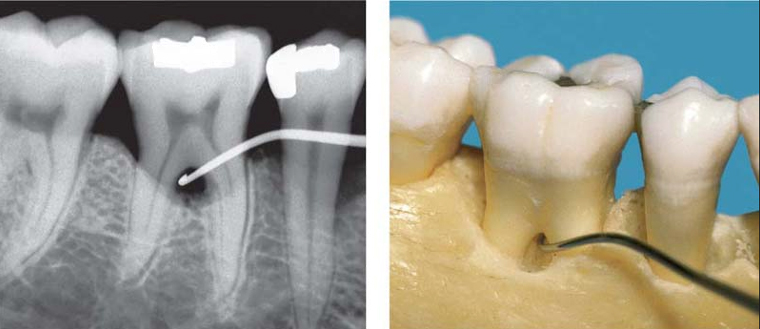

4/ Zabieg tunelizacji ma na celu zmianę warunków anatomicznych przestrzeni międzykorzeniowej pod zębem i umożliwienie lepszego oczyszczania tej okolicy. Wykonujemy go w sprzyjających warunkach anatomicznych (krótki trzon korzenia, szeroka przestrzeń międzykorzeniowa, długie korzenie). Zabieg można wykonywać tylko u pacjentów z bardzo dobrą higieną. Głównym powikłaniem jest próchnica korzeni obszaru furkacji.